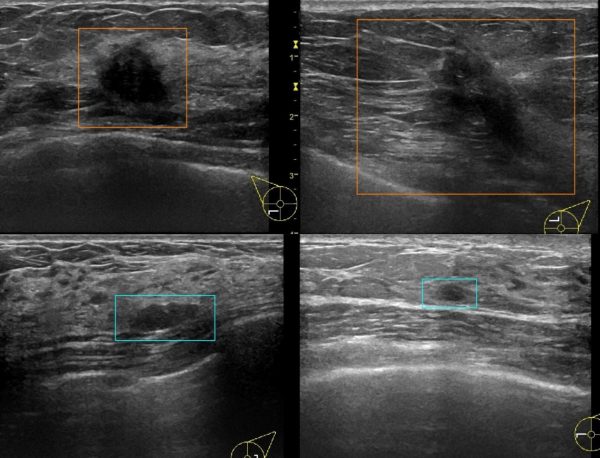

これらの背景から、本研究グループはAIの臨床応用を目指すにあたり、良悪性の判断を行うのではなく、乳房超音波検査画像に含まれる病変が、この BI-RADS 基準において乳がんの頻度が高まる BI-RADS カテゴリー4 以上なのか、乳がんの可能性がほとんどない BIRADS3以下なのかを判定するAI診断システムを構築した(図1)。

図1 AI が病変を認識し、BI-RADS4以上(精密検査が必要)ならばオレンジ、BI-RADS3以下(精密検査は必要なし)ならば青枠で表示